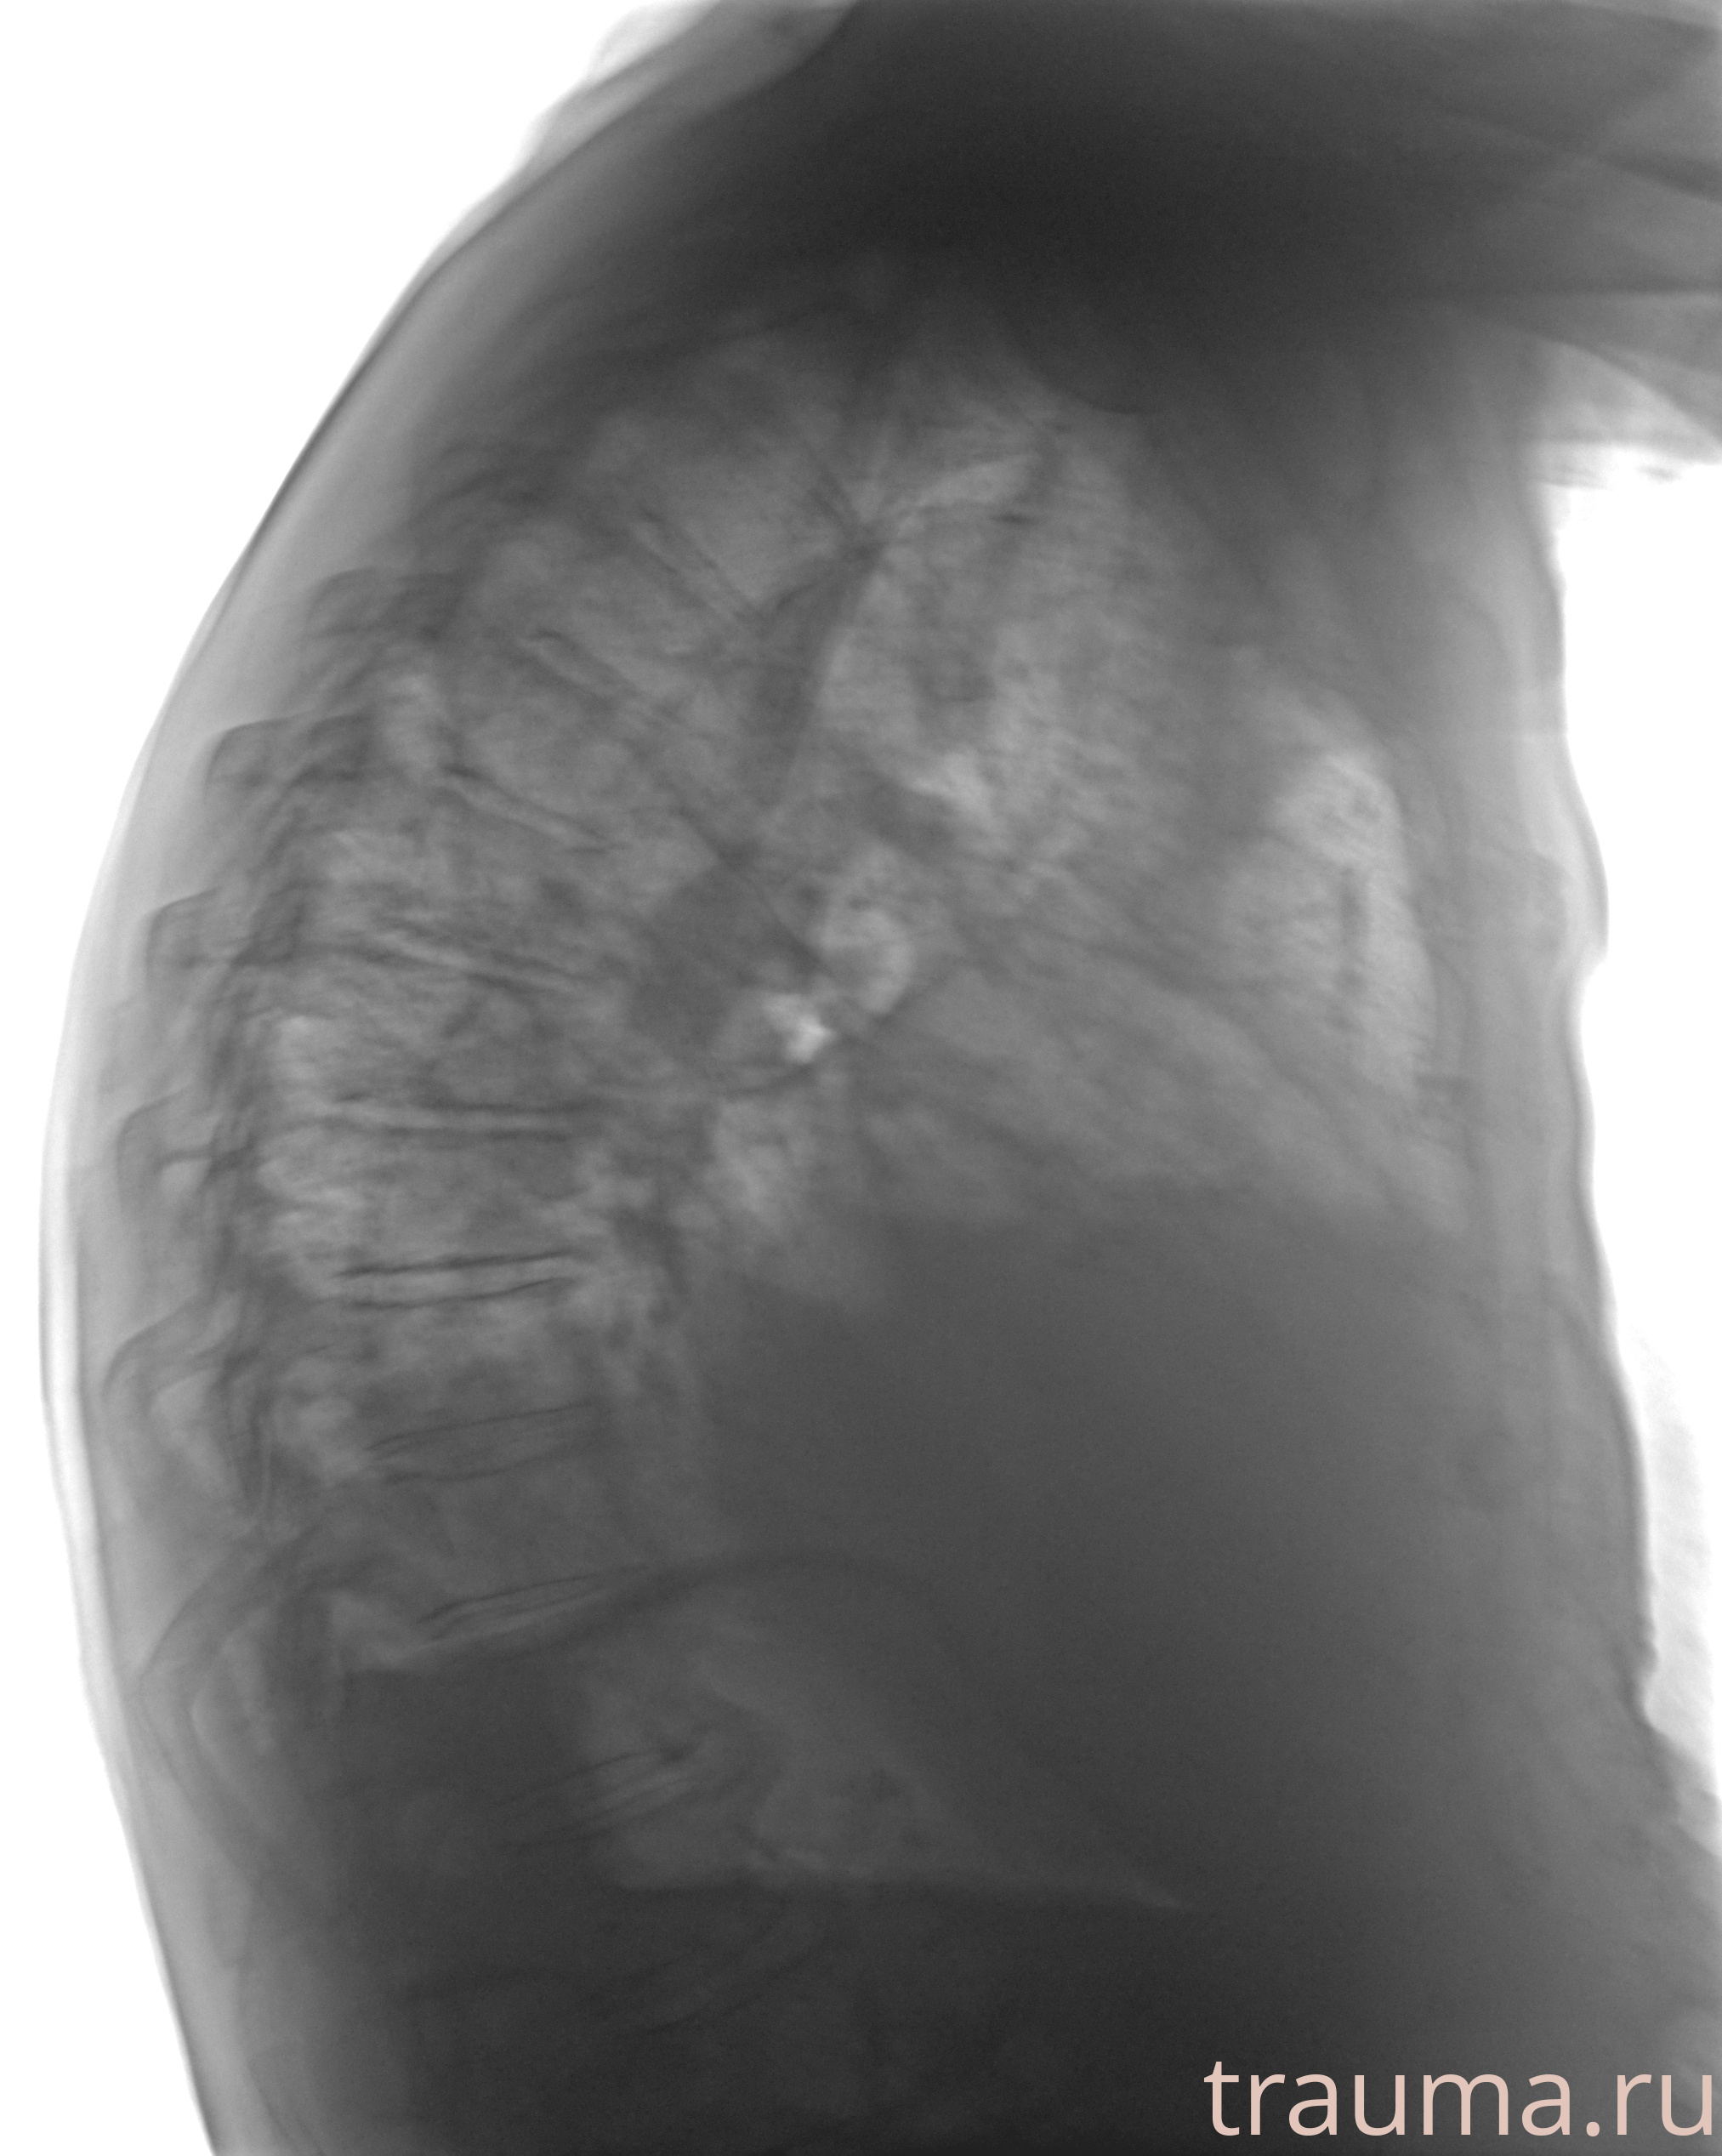

Рентгенограммы

Рентген на дому: по вашему адресу приезжает врач-рентгенолог, травматолог-ортопед с мобильным рентгеновским аппаратом, проводит диагностику травмы или заболевания, делает необходимые рентгенограммы, дает рекомендации по дальнейшему лечению. Получить качественные снимки в домашних условиях возможно благодаря уникальной методике, разработанной МосРентген Центром для института  Склифосовского

при переломе шейки бедра и пневмонии от компании МосРентген Центр - партнера Института имени Склифосовского